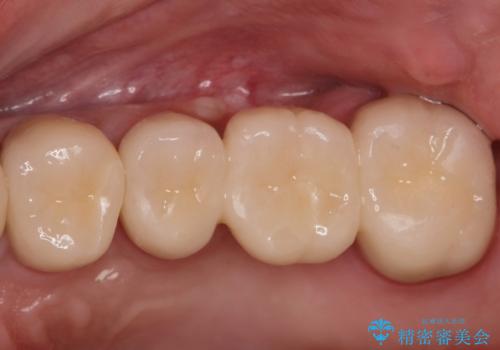

適合の良い被せ物、インプラントが入りました。

全ての治療が終わった後はNG(ナイトガード)を使用し、定期的にメンテナンスに

くることをお勧めしたいます。